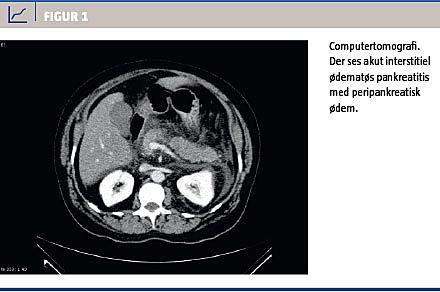

Billeddiagnostisk findes der flere forskellige graderingssystemer til bestemmelse af sværhedsgraden af akut pankreatitis. Mest anvendt i den morfologiske klassificering er Modified CT Severity Index [8] eller CT Severity Index [1]. Nekroser i pancreas og i det peripankreatiske væv udvikles først fuldstændigt flere døgn efter symptomdebut, og tidlige undersøgelser kan derfor medføre, at den egentlige udbredelse af nekroserne undervurderes [1, 2]. Udvidet billeddiagnostik til vurdering af pancreasnekroser og peripankreatiske komplikationer (Figur 1) bør derfor normalt tidligst udføres fire døgn efter symptomdebut (ikke indlæggelse), men kan om muligt under hensynstagen til patientens tilstand udføres så sent som ti døgn efter symptomdebut [1].